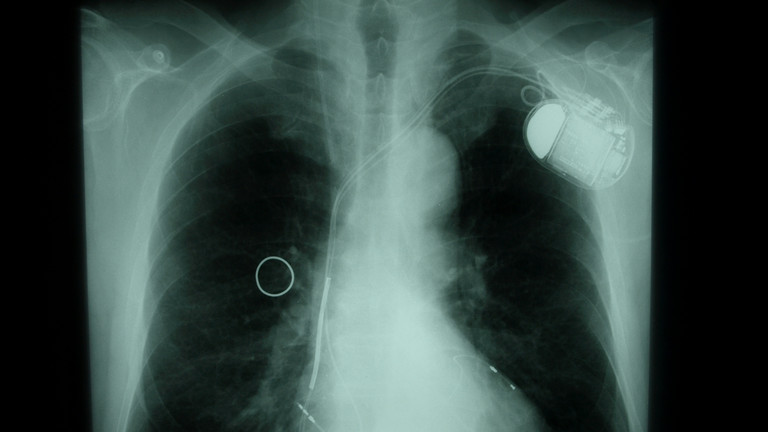

Sie profitieren von der Versorgung mit einem kardialen Device vom Schrittmacher über den Defibrillator bis hin zur kardialen Resynchronisationsbehandlung (CRT) oder Kunstherzimplantation (LVAD). Im Jahr 2018 wurde das Albertinen Herz- und Gefäßzentrum am Standort Albertinen Krankenhaus als hamburgweit erstes „Überregionales Heart Failure Unit-Zentrum“ zertifiziert.

Herzschrittmacherimplantation: 1-Kammer, 2-Kammer, 3-Kammer (CRT), kabelloser Herzschrittmacher ("leadless" Pacer)

Defibrillatorimplantation: 1-Kammer, 2-Kammer, 3-Kammer (CRT), Subkutaner Defibrillator (S-ICD)